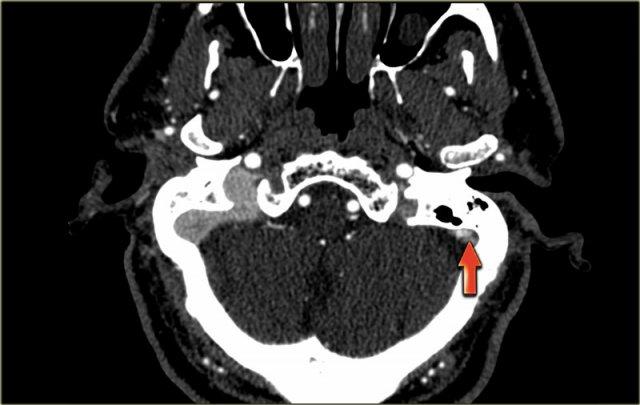

Nhồi máu tĩnh mạch (3) – Tĩnh mạch Labbe

Một dạng nhồi máu tĩnh mạch điển hình khác là do huyết khối tĩnh mạch Labbe.

Hình ảnh bên trái cho thấy giảm tỷ trọng ở chất trắng và ít rõ hơn ở chất xám của thùy thái dương trái.

Chẩn đoán phân biệt rộng bao gồm nhồi máu động mạch, nhiễm trùng, u não, v.v.

Lưu ý có một số đường tăng tỷ trọng trong vùng nhồi máu.

Đây là do xuất huyết.

Trong chẩn đoán phân biệt, cũng cần xem xét nhồi máu tĩnh mạch trong vùng phân bố của tĩnh mạch Labbe.

Tỷ trọng tăng nhẹ ở vùng xoang ngang trái (mũi tên) là chìa khóa để chẩn đoán.

Đây là dấu hiệu trực tiếp của huyết khối và bước tiếp theo là chụp CECT, xác nhận chẩn đoán (không hiển thị).